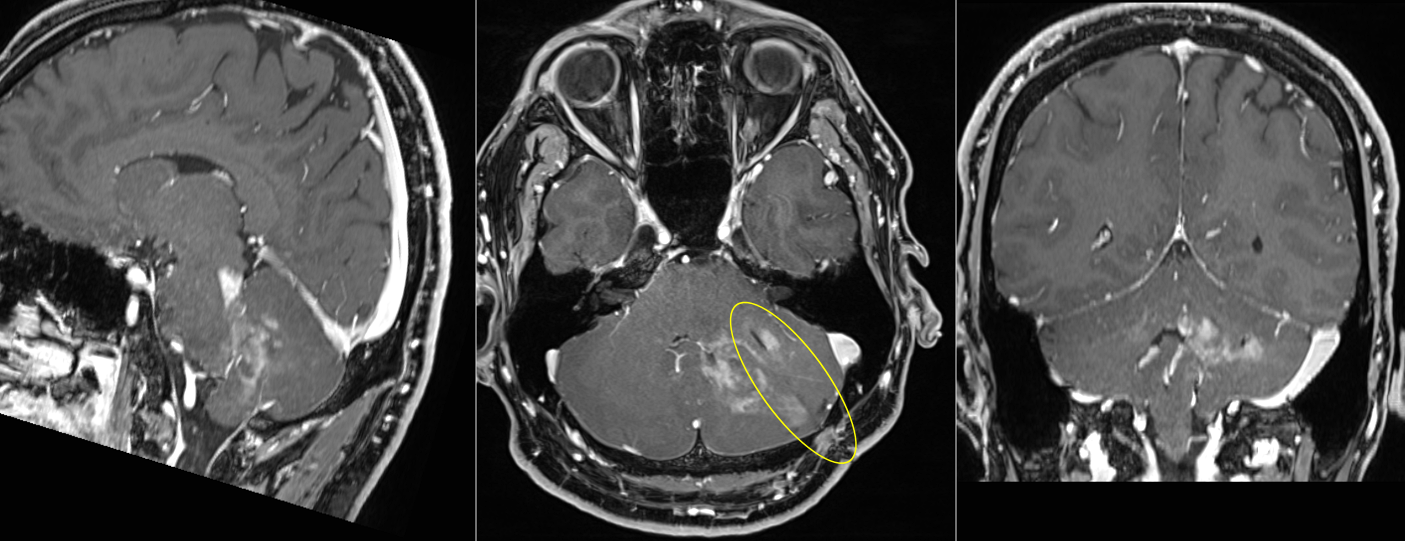

Ce presupune o biopsie ghidată prin neuronavigație? Se utilizează un RMN obișnuit, cu secțiuni fine, la 1-2 mm. (protocol 3D), pe care să fie vizibilă tumora (de obicei T1 cu contrast sau FLAIR). Acest RMN va funcționa ca o hartă pe care o încărcăm în stația de neuronavigație – GPS-ul -, iar corelarea dintre hartă și situația din teren – pacientul anesteziat – se face cu un instrument asemănător unui creion sau arătător (pointer). După ce avem o corelație bună între imaginea 3D și pacient (eroarea medie este de 0,9 – 1 mm.), se folosește un pointer special atașat de acul de biopsie care ne permite să navigăm cu precizie și să prelevăm țesut tumoral de unde dorim, urmărind poziția vârfului acului în timp real pe ecranul stației de neuronavigație.

Această metodă este mult mai comodă decât sterotaxia, atât pentru pacient, care nu mai este nevoit să stea cu cadrul fixat pe cap, cât și pentru chirurg, care nu mai trebuie să calculeze coordonatele țintei și să le transpună pe cadrul de sterotaxie. În ceea ce privește precizia, fiind o metodă “free-hand”, este mai puțin performantă decât biopsia streotaxtică, însă suficient de precisă pentru 99% dintre tumorile cerebrale. În plus, există brațe mobile care permit fixarea poziției acului de biopsie astfel încât să obținem precizia maximă, atunci când avem o tumoră mică, localizată în profunzime.